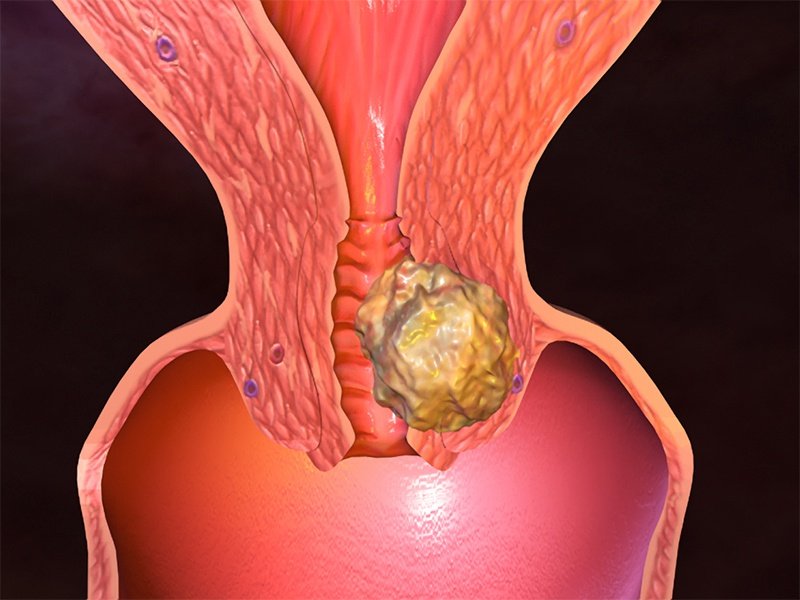

Анатомия женского организма: строение и функции матки